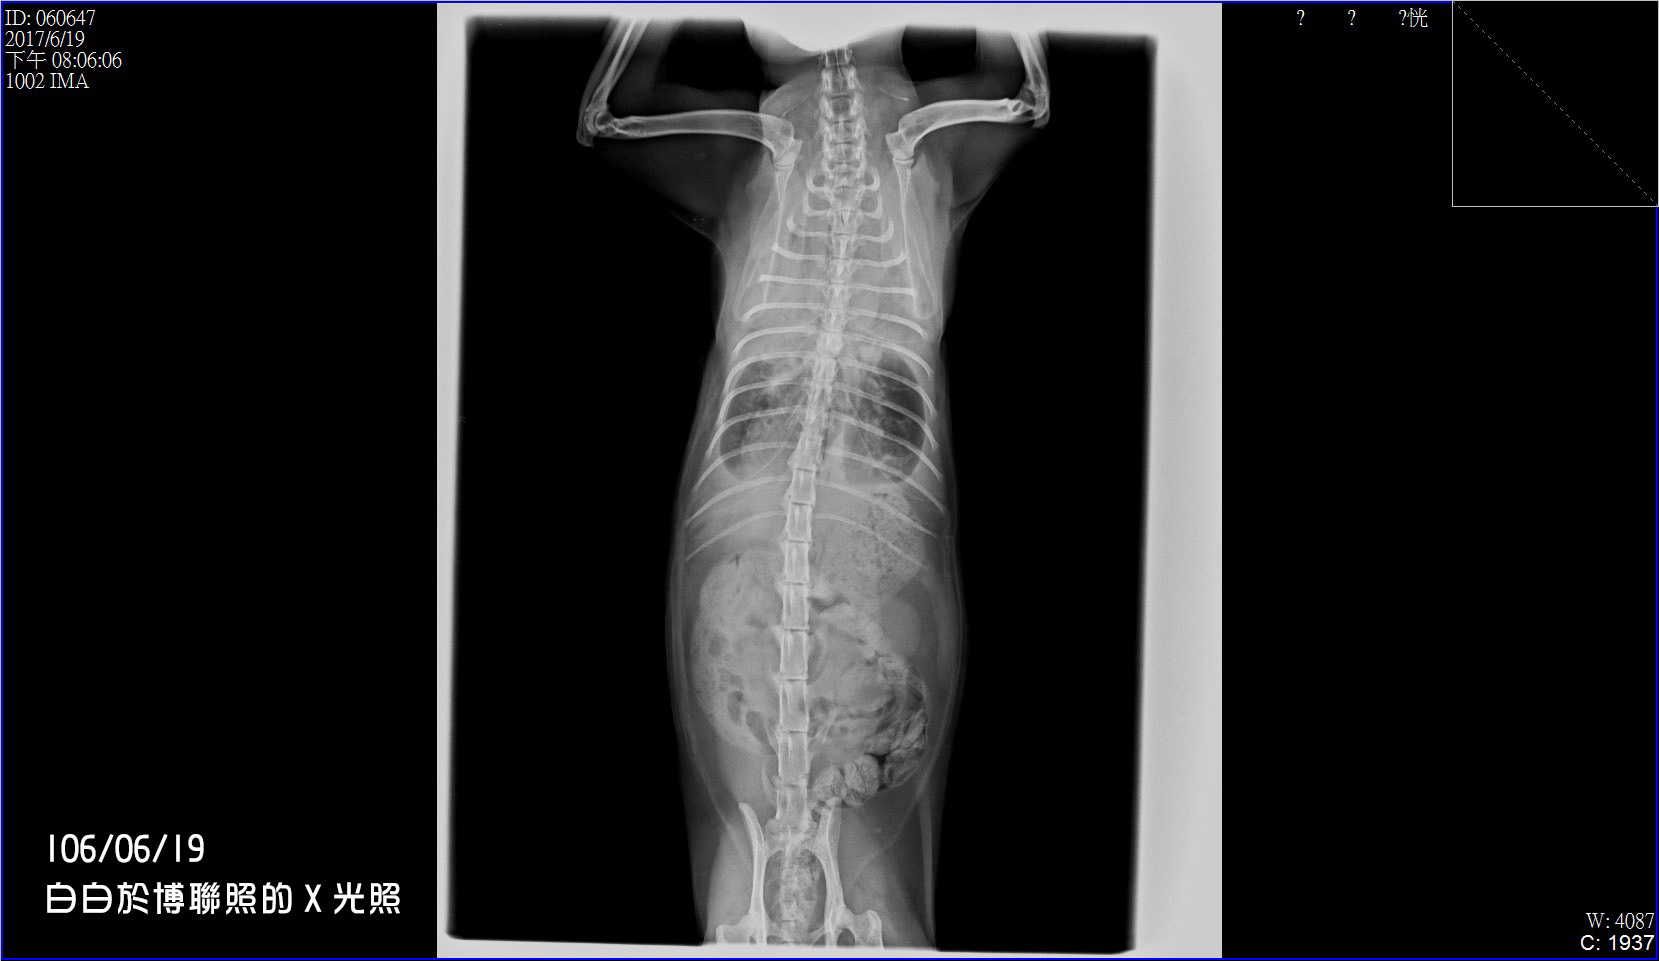

6/19下班後,我準備了所有資料與白白到了博聯,

醫生先照了X光片後,就發現白白的心臟比一般貓大,

於是開始進行照心臟的超音波ㄧ系列的檢查。

在這項檢查裡檢查出白白有「心房隔離缺損」,

二尖瓣閉鎖不全、三尖瓣閉鎖不全,導致心臟擴大。